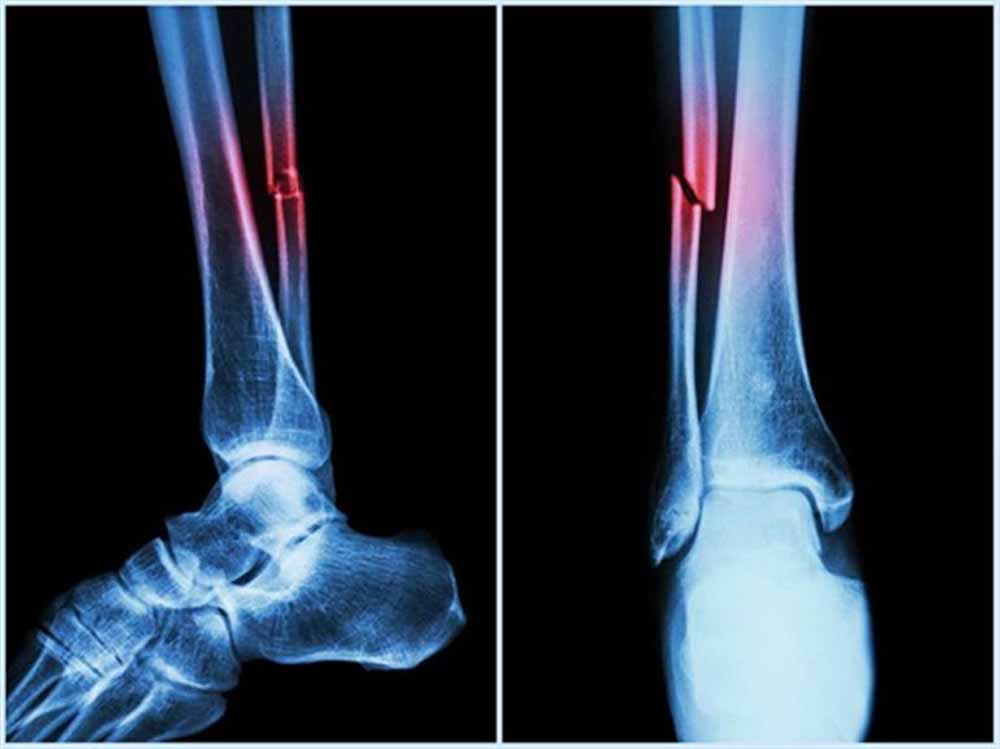

राष्ट्रीय प्रौद्योगिकी संस्थान (एनआईटी) राउरकेला के शोधकर्ताओं ने मानव शरीर में पाई जाने वाली प्राकृतिक शर्करा जैसे अणु हड्डियों के निर्माण और मरम्मत के लिए जिम्मेदार प्रोटीन, बोन मॉर्फोजेनेटिक प्रोटीन-2 के व्यवहार को कैसे प्रभावित कर सकती है? इसका पता लगाया है।

प्रतिष्ठित पत्रिका बायोकैमिस्ट्री में प्रकाशित इस शोध के निष्कर्षों का उपयोग हड्डी और उपास्थि पुनर्जनन के उन्नत उपचार, बेहतर इम्प्लांट और अधिक प्रभावी प्रोटीन-आधारित दवाओं के विकास में किया जा सकता है। प्रोटीन मनुष्य के शरीर में विभिन्न कार्य करते हैं। टिश्यू के निर्माण और रासायनिक प्रतिक्रियाओं में सहयोग देने से लेकर कोशिकाओं के बीच संकेतों के रूप में कार्य करने तक बड़ी जिम्मेदारी निभाते हैं।

हालांकि सर्वोत्तम उत्पादकता के लिए इनका त्रि-आयामी आकृतियों में सटीक मुड़ना या खुलना आवश्यक है। प्रोटीन क्यों और कैसे खुलते हैं? यह समझना जीव विज्ञान का एक प्रमुख लक्ष्य है। इसका प्रभाव चिकित्सा, जैव प्रौद्योगिकी और ड्रग डिलिवरी पर पड़ता है। इस संदर्भ में हड्डी और उपास्थि के निर्माण, चोटों को ठीक करने और स्टेम कोशिकाओं को अस्थि-निर्माण कोशिकाओं में परिणत करने में बीएमपी-2 महत्वपूर्ण भूमिका निभाता है।